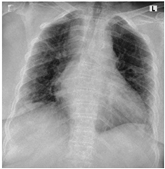

Furthermore, some of the examples of the COVID-19 positive and the healthy patients from the dataset are included in Table 5. The clinical data represent the attributes sequence, i.e., gender, age, body temperature, pulse rate, respiratory rate, blood pressure systolic, blood pressure diastolic, shortness of breath, cough, other symptoms, diabetes mellitus, hypertension, cardiac disease, dyslipoproteinemia, chronic kidney disease, and other chronic diseases.

Table 5.

Sample CXR and clinical data for the COVID-19 positive and healthy cases.